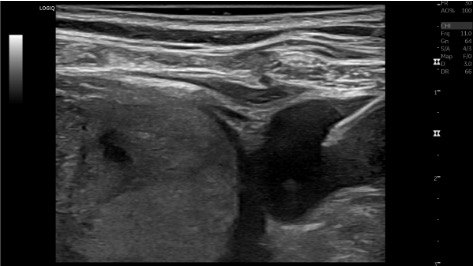

View IJ US access

Ultrasound of internal jugular vein access